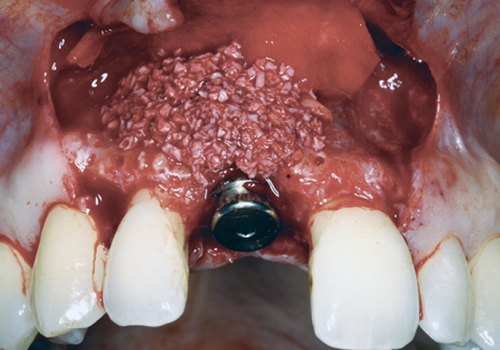

Bərpa texnikasının müəyyən edilməsi, sümüyün hansı bölgədə, hansı miqdarda itirilmiş olmasına bağlı olaraq müəyyənləşdirilir. Bərpa üçün tətbiq edilən sümük materialları pasiyentin öz donor bölgələrindən xüsusi metodlarla qazanılmış sümüklər, o cümlədən digər fərdlərdən alınmış və xüsusi qaydada hazırlanmış materiallar, heyvan mənşəli sümükəvəzləyici materiallar və sintetik materiallar olaraq ayrılır.

Bərpa zamanı yerinə görə bu materiallar ya ayrı-ayrılıqda, ya da kombinə olunmuş şəkildə tətbiq oluna bilir. Gündəlik təcrübədə həmçinin pasiyentdən götürülmüş qan nümunələrindən alınmış yüksək bərpaedici xassəyə malik materiallar (PRF) da uğurla tətbiq olunur. Sümükartırma metodlarının tətbiqi sayəsində, çənədə implantların yerləşdirilməsi üçün yetərsiz sümük həcmi olan bölgələrdə sümük miqdarı yetərli duruma gətirilir, uyğun boy və diametrə uyğun implantlar uğurla tətbiq olunur.